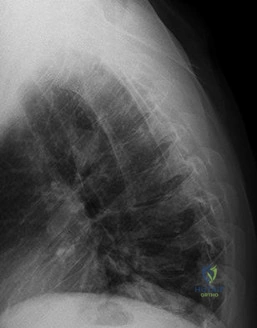

A 12-year-old obese male presents with chronic left groin pain and an obligatory slip into external rotation with passive hip flexion. Radiograph of the hip is shown.

Which of the following represents the strongest indication for prophylactic in situ pinning of the contralateral, asymptomatic hip in a patient with a Slipped Capital Femoral Epiphysis (SCFE)?